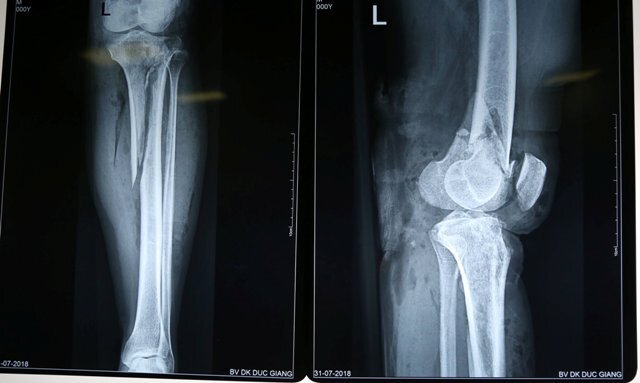

Bệnh viện Đa khoa Đức Giang vừa phẫu thuật thành công cho một nam bệnh nhân gãy chân và tổn thương mạch máu do tai nạn giao thông.